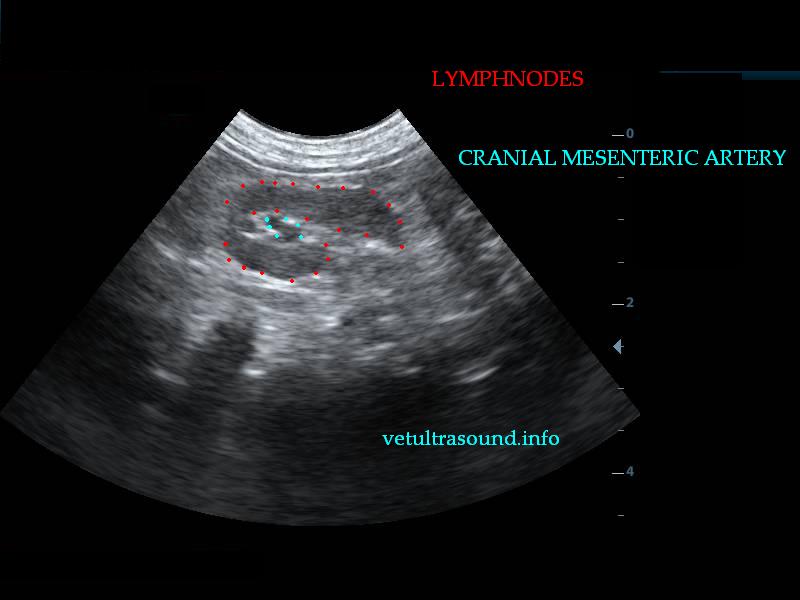

Findings: There was a mild enlargement of the mesenteric lymphnodes(pic3). In a small segment of the small intestine a cyst was noted which was attached to the intestinal wall(pic2.3). There were also dilated intestinal loops before the cyst due to the narrowed intestinal lumen. No free fluid was noted. There was a mild increase of the mesenteric fat arround the cyst.

Treatment: Surgical removal of the intestinal cyst.(pic4)

Θεραπεία: Έγινε χειρουργική αφαίρεση του τμήματος. (pic4)